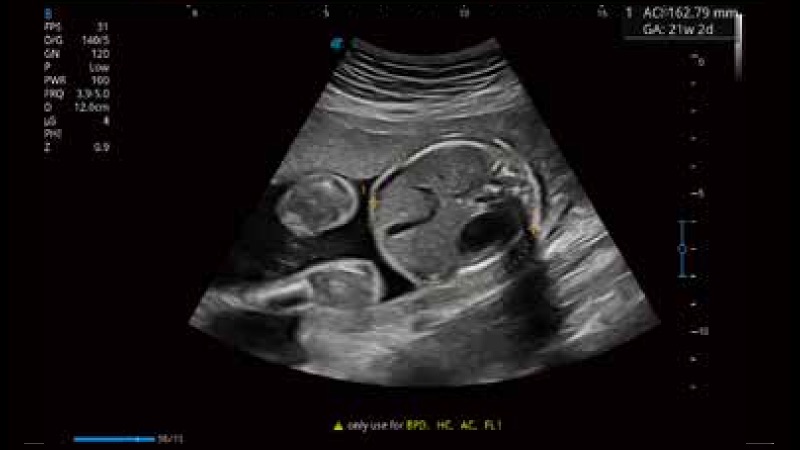

S-Fetus 产科扫查助手

S-Fetus基于大数据深度学习算法,能够帮助您在产前筛查过程中智能识别胎儿标准切面、自动测量并录入报告。一个按键,即可智能、精准、高效地获取胎儿生理指标,极大简化您的产科检查操作。

临床图像